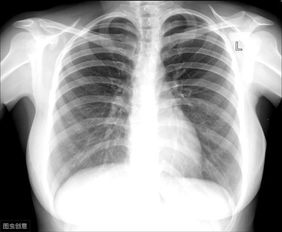

“胸片曝光”指的是使用X射线对患者胸部进行成像的过程,X射线是一种电磁辐射,能够穿透身体不同密度的组织,在胸片上,密度高的组织(如骨骼)会呈现为白色,密度较低的组织(如肺部,充满空气)呈现为黑色或深灰色,而中等密度的组织(如心脏、大血管、肝脏、脾脏等)则呈现为不同的灰度,通过观察这些影像信息,医生可以判断是否存在异常,如肺炎、肺结核、肺癌、心肌肥厚、胸腔积液、肺气肿、胸膜病变、骨骼异常等。

- 观察肺部: 正常肺野应该是深灰色(含气),如果看到大片白色或混杂区域,可能提示炎症、积液或纤维化,黑色区域如果异常扩大,可能提示肺气肿。

- 观察心脏和大血管: 心脏轮廓在胸片上大致呈“靴形”或“梨形”,如果心脏轮廓增大,可能提示心脏功能或结构问题,主动脉弓是胸片上重要的血管标志,增宽可能提示动脉瘤。

- 观察胸廓和骨骼: 肋骨、胸椎、锁骨等结构应排列整齐,无扭曲或异常增厚,胸腔内软组织密度均匀。